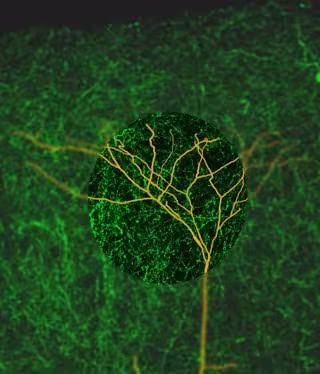

ARTWORK BY LEE FLETCHER, QUEENSLAND BRAIN INSTITUT

En concreto, el trabajo, publicado en la revista 'Neuron', ha demostrado que la actividad eléctrica del neocórtex del cerebro cambia cuando se enfoca atención, gracias a que las neuronas detienen la señalización sincronizada entre sí.

Concretamente, los expertos se preguntaron si las neuronas piramidales de la capa 5, las neuronas de "salida" del neocórtex, podrían estar involucradas en el sistema colinérgico porque están íntimamente involucradas en cómo se percibe el mundo. Usando una técnica llamada optogenética, modificaron las neuronas en el sistema colinérgico en los cerebros de los ratones para que pudieran activarse con un destello de luz azul, lo que provocó una repentina liberación de acetilcolina.

Esto permitió a los investigadores monitorear de cerca la interacción entre el sistema colinérgico y las neuronas de salida, descubriendo así que cuando las neuronas de salida recibieron información excitadora sobre sus dendritas, el sistema colinérgico aumentó masivamente su actividad.